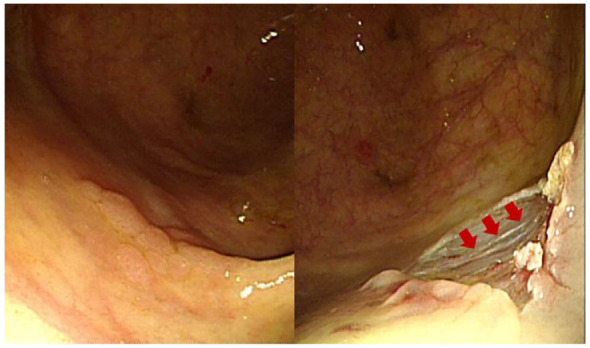

Results: Microperforations occurred in 12 patients (8 males; age: median 64.5 years). Polyps with microperforations were more frequent in the right colon (83.3% vs 33.3%). Endoscopic mucosal resection with precutting (EMR-P; 16.7% vs 0.0%) or hot-snare polypectomy (8.3% vs 0.0%) was more frequently performed in the microperforation group. Muscle fibers at the polypectomy site were more frequently visible in the microperforation group (58.3% vs 8.3%). By multivariate analysis, right colon location and visible muscle fibers were independent risk factors for microperforation. All patients with microperforation received intravenous antibiotics and were advised to fast. Patients responded well to these conservative treatments and were discharged after a median of 3 (2-6.75) days of hospital stay.

Conclusion: Our data suggest that conservative treatment is feasible and could be the primary management option for selected patients with microperforations postcolonoscopic polypectomy. Right-sided colonic polyps and visible muscle fibers predispose to microperforations.